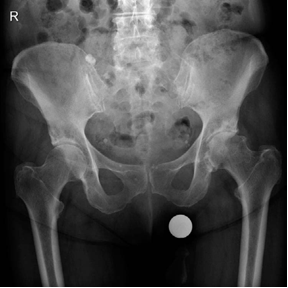

Structured Oral Hip Examination Question 3 EXAMINER : This is an anteroposterior (AP) radiograph of a 78-year…